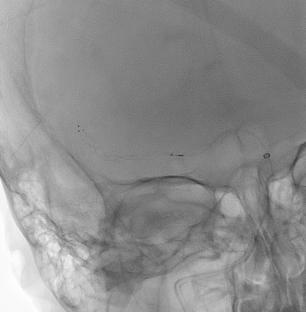

在经循环取栓术中,交通动脉通过后循环进入前循环,反之亦然。由于复杂的血管解剖结构或涉及颅外和颅内血管的慢性病变,传统的顺行血管内入路具有挑战性,该入路可用于患者。到目前为止,只有几篇文章讨论了这种方法。在这里,我们提出一个68岁的妇女谁提出了突然发作的左侧无力的情况下。CT血管造影显示右侧颈总动脉(CCA)闭塞,同侧大脑中动脉(MCA) M1段闭塞。通过后交通动脉(Pcomm)通畅,采用经循环入路对右MCA闭塞进行了成功的栓塞切除术。出院时,患者有轻度缺陷,随访1个月后完全恢复。我们的病例强调了这种技术的有效性和安全性,尽管有潜在的并发症,如延长手术时间。需要进一步的研究来优化患者选择和技术。

In a transcirculation thrombectomy, the communicating arteries are used to access the anterior circulation via the posterior circulation, or vice versa. This approach can be used in patients where traditional anterograde endovascular approaches are challenging due to complex vascular anatomy or chronic lesions involving extracranial and intracranial vessels. Up until now only a few articles addressed this approach. Here, we present a case of a 68-year-old woman who presented with a sudden-onset left-sided weakness. CT angiography showed an occlusion of the common carotid artery (CCA) on the right side and an ipsilateral occlusion in the M1 segment of the middle cerebral artery (MCA). A transcirculation approach was used to perform a successful embolectomy for the right MCA occlusion through the patent posterior communicating artery (Pcomm). At discharge, the patient had mild deficits and fully recovered at 1-month follow-up. Our case highlights the effectiveness and safety of this technique, despite potential complications like prolonged procedure time. Further research is needed to optimize patient selection and technique.